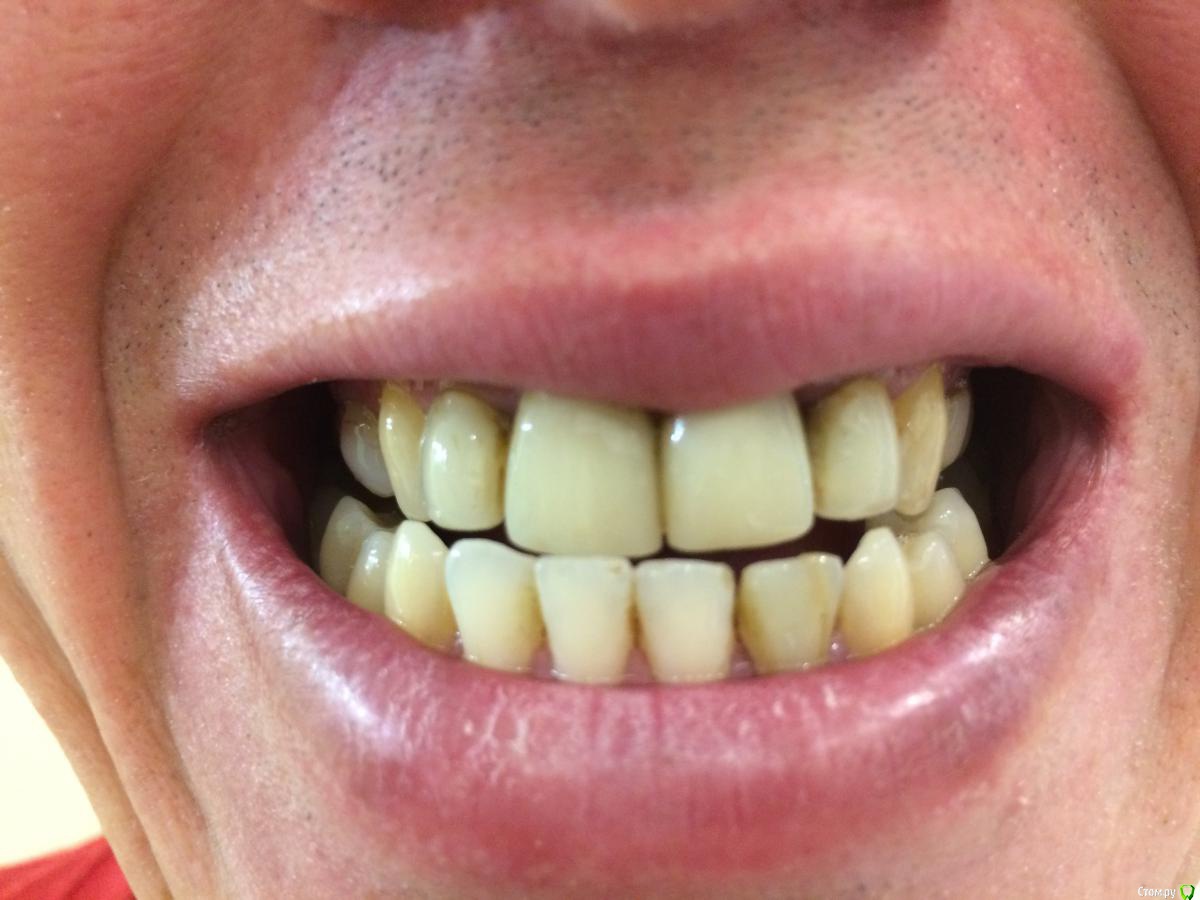

Мне 34 года, прикус мезиальный, наследственный. Решил исправить прикус. Есть нюанс по состоянию зубов, единицы, двойки, четверки и пятерки - коронки из композитного материала (световая пломба), после решения вопроса прикуса планирую заняться протезированием. Сходил к ортодонту, посоветовали съездить в Екб на консультацию в УГМУ. Съездил на консультацию, сказали что только операция с ортодонтической подготовкой до и после операции. При этом сказали, что удалять ничего не надо.